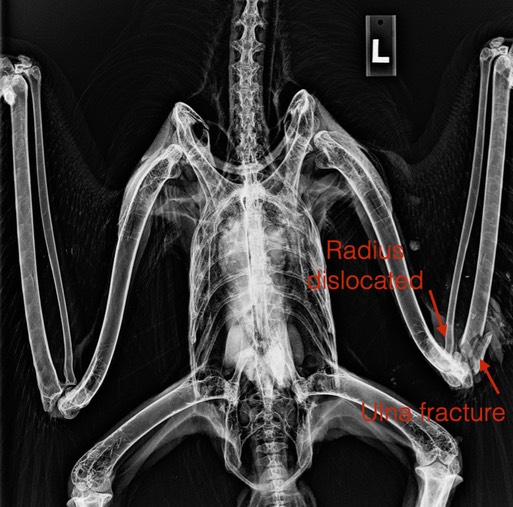

Earlier in the week a young Golden Eagle was admitted. The eagle was likely struck by a vehicle. He was extremely emaciated and had a dislocated left radius and a fractured ulna. The damage to the eagle's elbow was not repairable and he was euthanized.

Even if the wing had been repairable, I doubt if we could have saved him. The eagle weighed just over 4 pounds. A normal weight would have been 7 or 8 pounds. There is very little visible muscle mass in the radiograph above. Such extreme emaciation is very difficult to overcome.